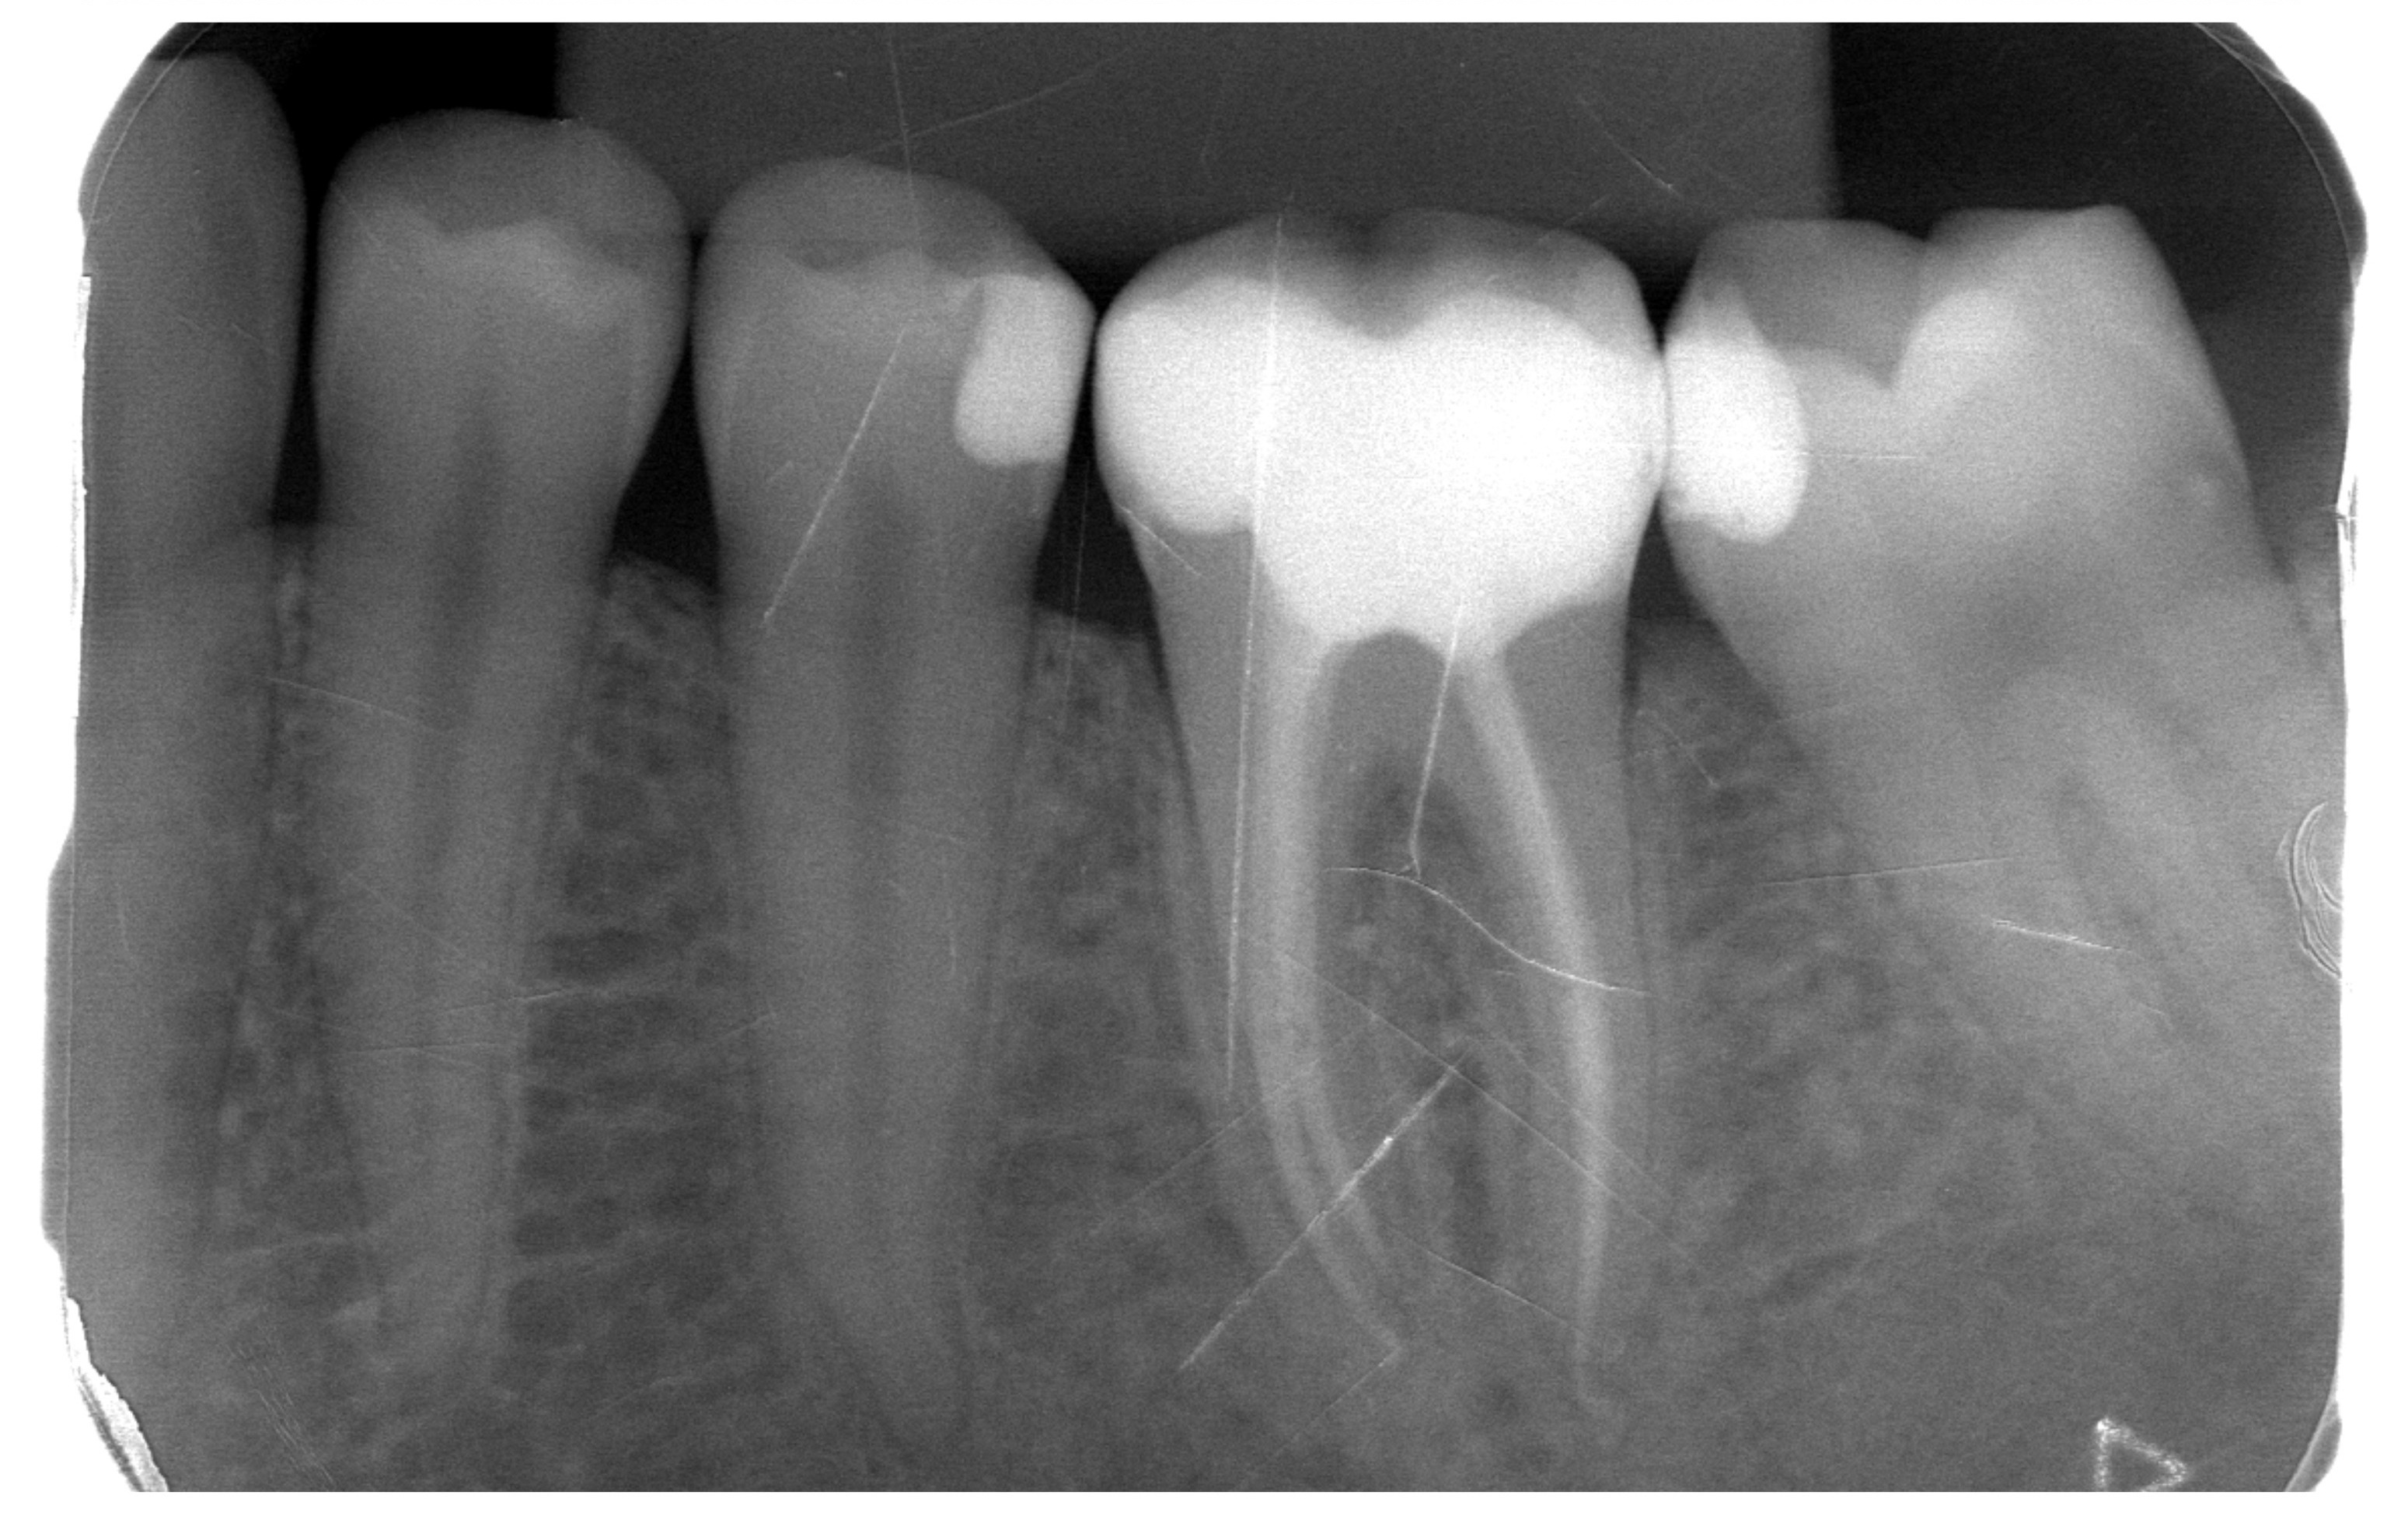

Initial X-ray – caries on lower second premolar and molars and first molar with gangrene

Control X-ray – treated root canals of lower first molar and fillings on premolar and molars